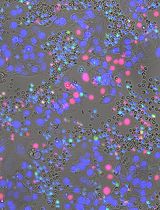

Here we utilise the GFP+-LUHMES which we previously generated and validated as a useful model for metabolic dysfunction, to present a detailed and reproducible protocol for high-throughput screening of compounds in a toxin-induced differentiated LUHMES cell model relevant to PD. This protocol improves on previous studies by using high-content live cell imaging and analysis to assess mitochondrial parameters and neuronal morphology.

In the approach described here, differentiated LUHMES cells are treated with rotenone to model PD-associated mitochondrial dysfunction and neuronal loss in accordance with previous studies (Krug et al., 2013; Dolga et al., 2014). LUHMES cells are grown to full confluency before the addition of differentiation factors, and then replated into 384-well plates after two days. The cells remain in differentiation media for the full time course of the experiment. The plate is treated with rotenone on the fifth day, then treated with test compounds on the sixth day and live imaged on the seventh day (Figure 1). When designing a toxin induced model for screening; there are generally two paradigms. The first being a protection model, where the potential beneficial compound is added to the cells before the toxin. Secondly, and is the case in this protocol, is a restoration model; where the toxin is added first and then the potential beneficial compounds are added afterwards. This is testing the beneficial compounds to restore a defect already present as opposed to protecting from damage occurring. The advantage of this technique lies in the relative ease and speed in generating a uniform population of disease-relevant human dopaminergic neurons that can be used for large-scale compound screening. Furthermore, high-content live cell imaging and analysis allows the assessment of compound dose-response effects on a broad range of mitochondrial and neuronal morphological parameters.